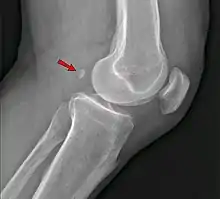

Genou

Aspect clinique

Un os surnuméraire peut provoquer un diagnostic radiographique érroné de fracture[19].